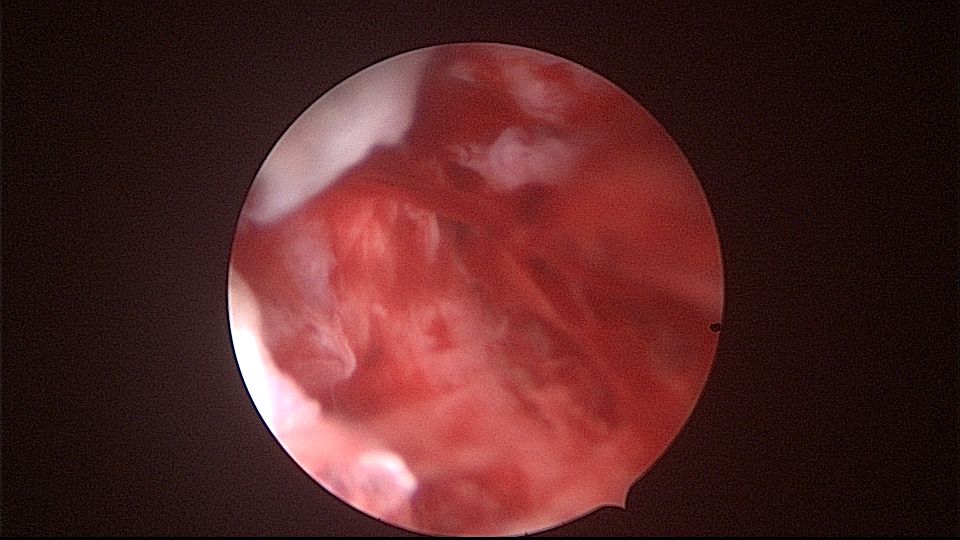

患者52岁,G2P1,顺产1次。安环27年,外院取环失败。病人肥胖,子宫极度前倾前屈位,宫腔镜见宫颈管组织杂乱,宫颈管上段右前壁见假道,膨宫不良,视野模糊,寻找宫腔方向困难,准备B超监护过程中,拆走扩阴器,腹部下压子宫,终于寻找到了宫颈内口,看到了爱母环下端,异物钳牵拉出节育环,再次探查宫腔,无其他异常。